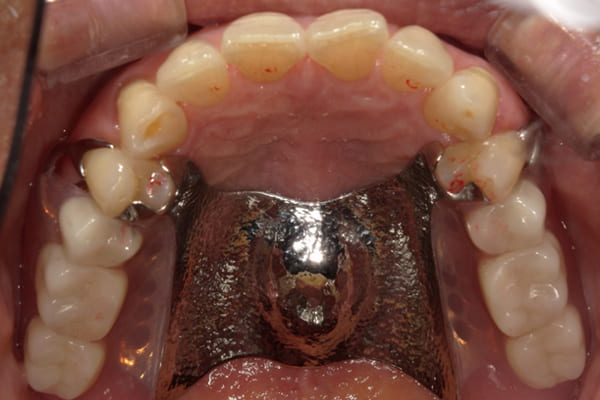

症例レポート[CASE.04]

前歯がとれて痛い、

食事もできず、見た目も悪い

- 性別・年齢

- 女性(60代)

- 主訴

- 前歯がとれて、痛い、食事ができない、見た目が悪く人に会えないので何とかしてほしい

- 治療

-

- 上顎精密金属総入れ歯

- 下顎精密金属部分入れ歯

- 磁性アタッチメント(白金加金) 1歯

- 治療期間

- 約5か月間

- 費用

- 上顎精密金属床総入れ歯:55万円

- 下顎精密金属床部分入れ歯:55万円

- 磁性アタッチメント:11万円×1歯

(白金加金)

合計:121万円(税込)

上前歯はブリッジの差し歯により根が折れ炎症を起こしお痛みのある状態でした。

原因は長期使用により下の義歯の歯が削れたことにより、下前歯が上前歯を突き上げ強い力が加わっていたことが根本的な原因と考えられます。

治療前は、奥歯が下がり、かみ合わせが乱れています。適切な入れ歯はそのままのかみ合わせで義歯を作るのではなく治療後のように、前歯から奥歯までのラインが真っすぐ揃った、かみ合わせの面を適切に付与し、よく咬め、残りの歯に負担がかからないかみ合わせとしました。

とにかく何も食べられないこと、人に会えないことから、なるべく早く何とかしたいとのご希望でした。

患者様とご相談の上、まず早急に上記を回復させるため、初診含め3度の来院でお食事ができ、見た目を回復できるように治療用義歯を作製、装着しました。

本来は、数本の上前歯の折れてしまって残せない歯は抜いてから歯肉の治癒を待ち、数か月後に型どりから作製になりますが、抜歯即時義歯といって、歯を抜く前に型、かみ合わせをとり、抜歯を行ったその日に上下の義歯を装着する特殊な治療法を用いたことで、10日後には治療用義歯をお口に装着することができ、お痛みもなくお食事ができ、ご友人とのお食事にも行けることが可能になりました。

本来、入れ歯作製は技工所と言って、義歯を作製する所に発送するため、作製には時間がかかりますが、院内に技工専用スペースを完備しており、長年、義歯治療において、技工も技術の習得してきましたので技工士さんではなく、かみ合わせの道具も私自身で院内で作製したことで、初診日の次の日にご来院いただきかみ合わせを採ることで、診断、型どり、かみ合わせ、装着まで10日という最短のご希望にこたえらた方です。

ここから、最終的な義歯の作製は従来通り行いました。

抜歯した歯肉が治癒するのを待っている間に、細かなかみ合わせ調整や、審美的なご希望、違和感などをお伺いしそれをもとに、最終義歯を作製しましたが、その作製中も治療用義歯は快適にお使いいただけるため、普段の生活を行いながら通院していただくことが可能となりました。

お写真は治療用の仮の入れですが普段通りお食事ができるとのことで少し食べ物もついています。。。

上顎治療前

上顎治療後

根のみの7本は虫歯にもなっており歯肉は腫れあがっています。

残りの歯もレントゲンで重度の歯周炎によりぐらぐらな状態でした。

下顎治療前

下顎治療後

治療前の入れ歯の奥歯は、治療後の義歯と比較しても分かるように、歯が削れ平らになった状態です。

これにより奥歯のかみ合わせは低くなり、前歯のみが強くあたり、かみ合わせにより上の前歯大きな負担がかかっていたことにより、上の前歯が折れたことが考えられます。